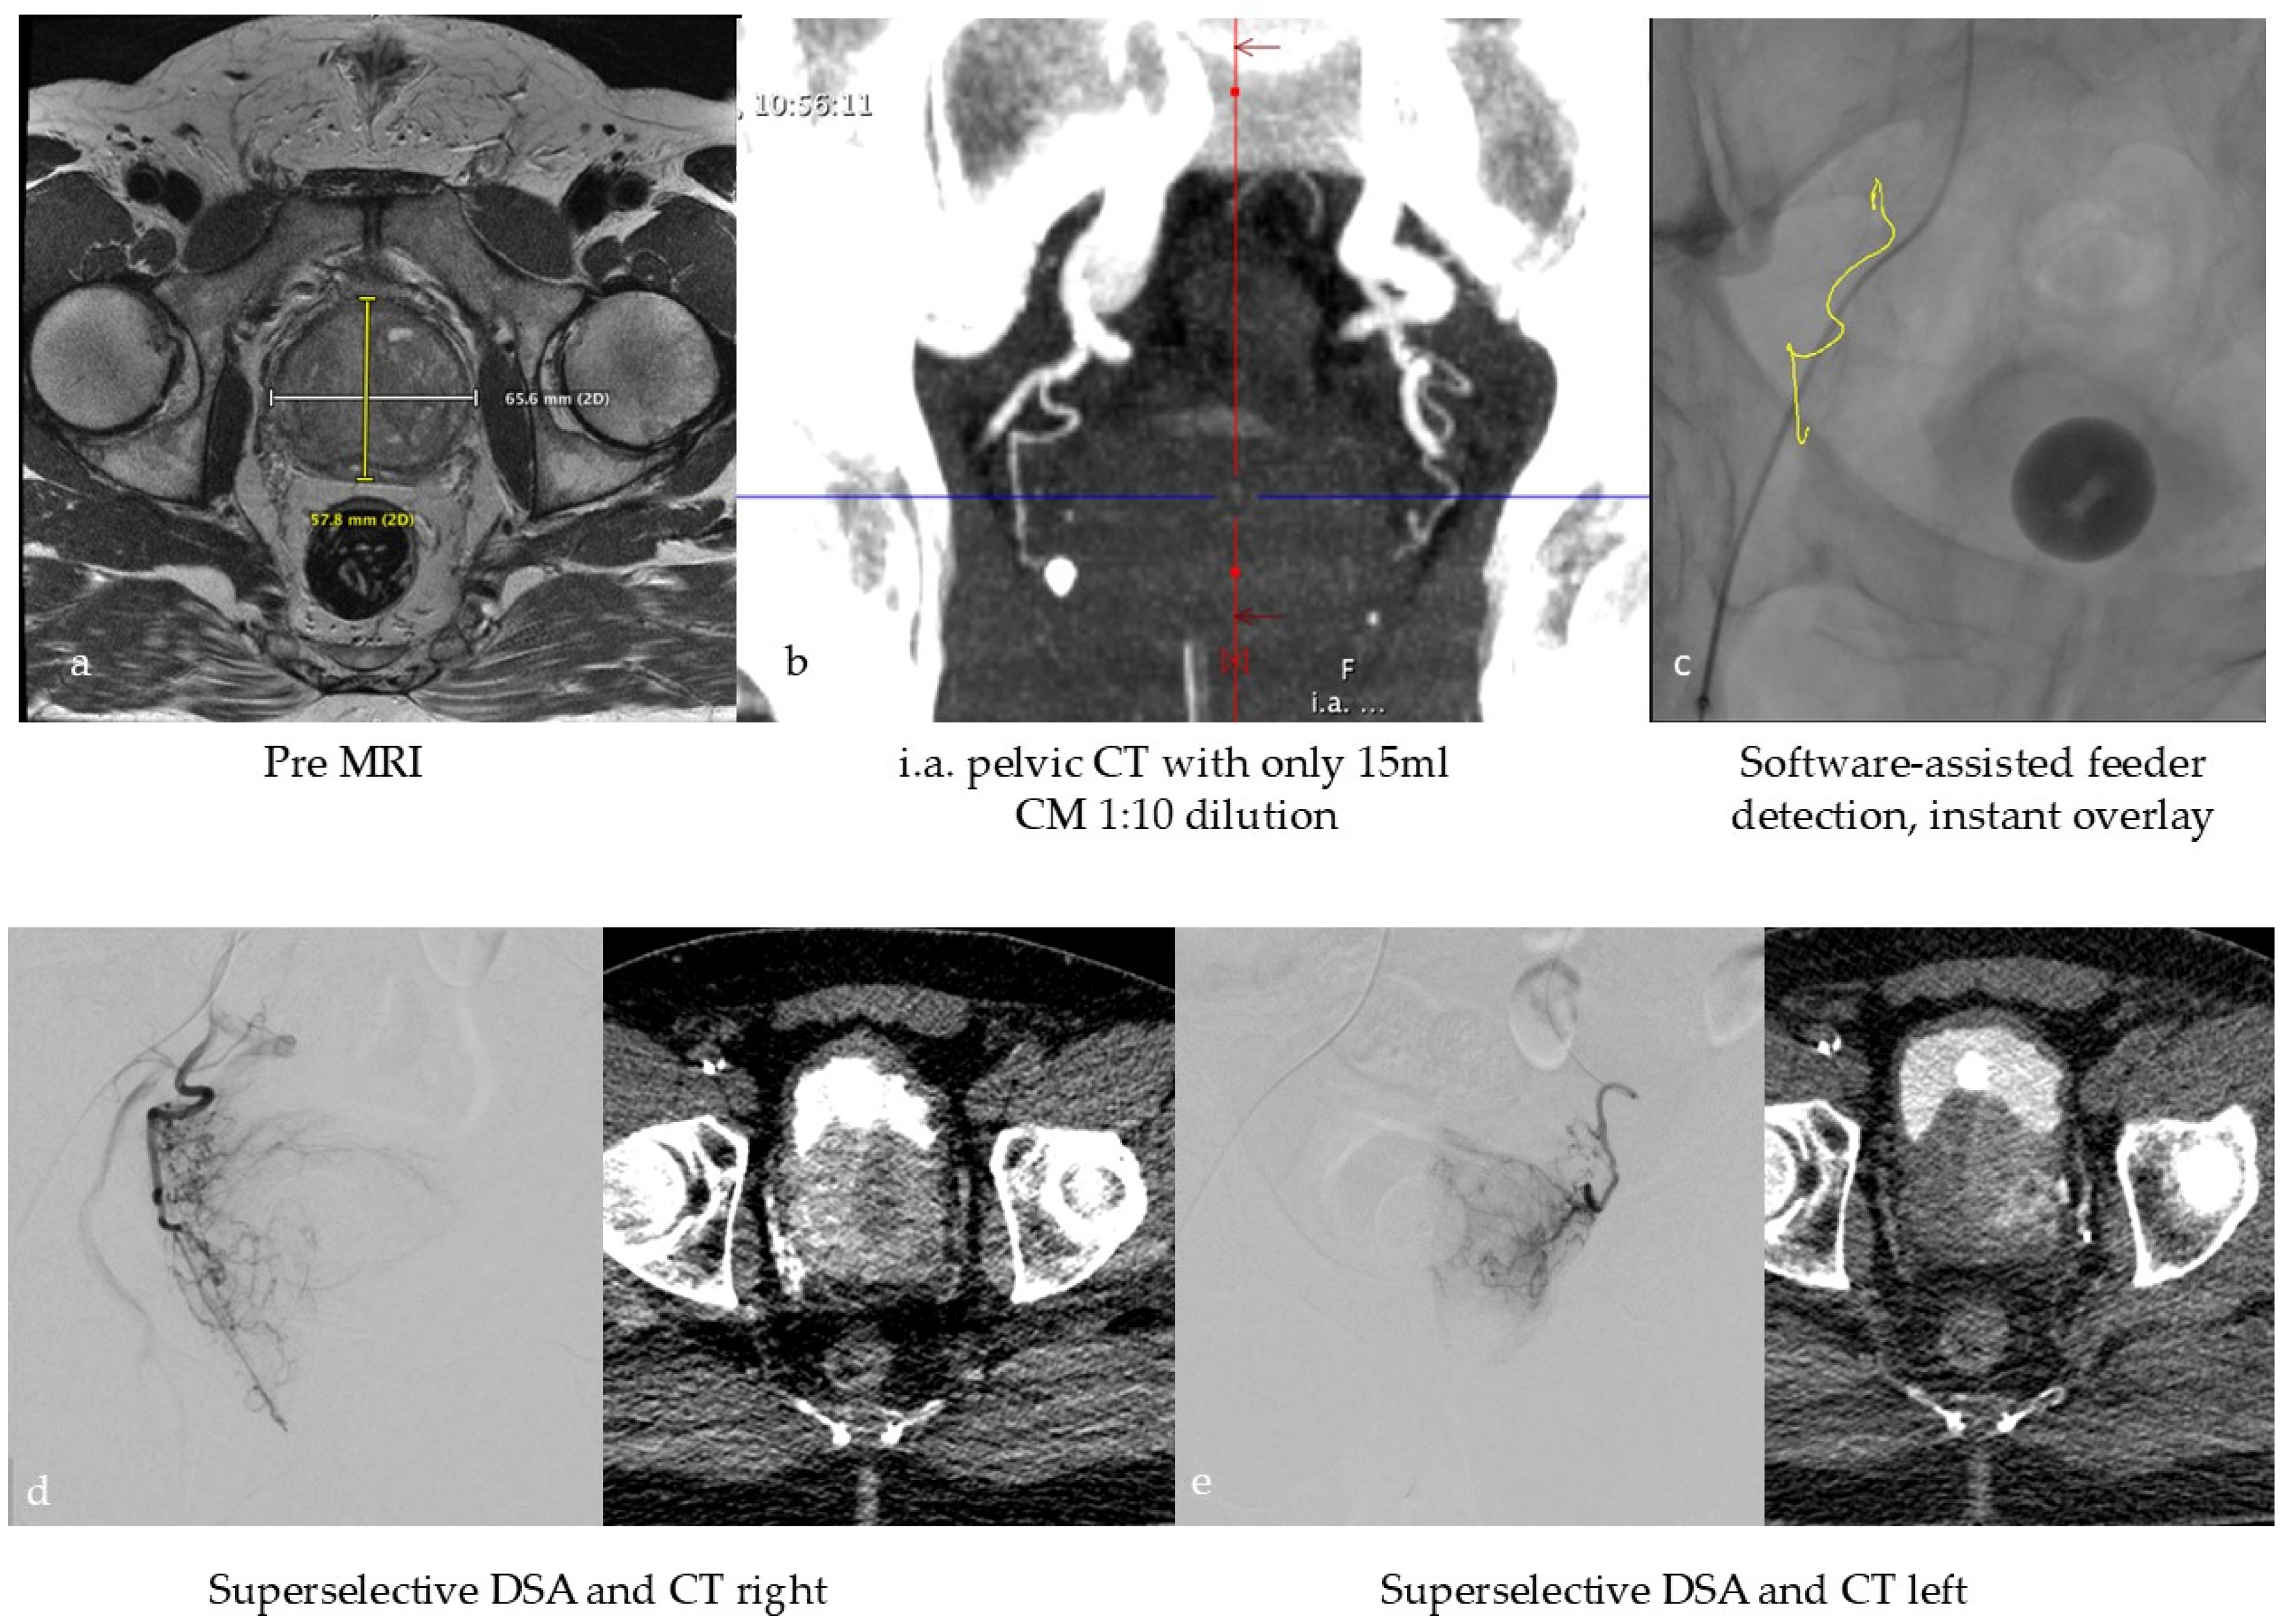

Figure 2. Typical workflow for prostatic artery embolization in benign prostatic hyperplasia (BPH): (a) optional pre-interventional MRI to visualize the hyperplasia and exclude tumors, (b) intra-arterial CT angiography with 100 mL volume, with 1:10 dilution corresponding to approx. 10 mL CM at the beginning of the intervention to identify the prostate arteries, (c) software-based marking of the prostate artery and overlay on fluoroscopy, (d,e) After super-selective probing of the right and left prostate artery, DSA and CT were performed to ensure selective targeting of prostate tissue.

In the context of tissue devascularization procedures, the concept of super-selective treatment assumes particular significance in the scope of PAE for the treatment of symptomatic BPH, given the notable proximity of the structures at risk. The success of the treatment depends on the identification of the tiny, highly variable feeding vessels and their collaterals [59,60]. This leads to relatively complex procedures with potentially increased radiation dose to the patient and medical staff. Due to the lack of adequate imaging in the early days of PAE, complications due to ischemia in the rectum, bladder, and penis sometimes occurred, although rarely [60]. Consequently, the current consensus on the imaging workflow involves performing a preprocedural CT or MR angiography followed by an intraprocedural selective CBCT scan of each internal iliac artery to identify the relevant feeding prostate arteries. In the second step, the end-stream route intended for embolization must be verified by an additional distal super-selective CBCT to avoid complications associated with non-targeted embolization [61]. As preoperative cross-sectional imaging is not part of the routine BPH clinical workup, a group of experts recently published an innovative viewpoint to perform PAE without preprocedural CT or MRI but in a single session with high-resolution intraprocedural imaging. The authors of this study hypothesize that an Angio-CT suite will allow for a dedicated one-stop workflow with high soft tissue contrast planning images without motion artifacts, like conventional ceCT, and excellent super-selective imaging for precise targeting [62]. This workflow is illustrated in Figure 2.